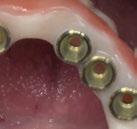

Ejecución técnica protésica

Dado que la estabilidad primaria se ha conseguido en la mayoría de los implantes, coincidiendo con la previsión propuesta en la planificación, procedemos ahora a la fase protésica. En el caso que nos ocupa, la paciente reside lejos, por lo tanto, colocamos tapones sobre los pilares transepiteliales y descansa en la sala de recuperación (Figura 30).

El procedimiento de diseño, impresión, pulido y cementación de aditamentos consume

aproximadamente una hora y media. Usamos resina Bego VarseoSmile TriniQ® para puentes definitivos. Aunque en este caso la vamos a usar para confeccionar unas prótesis fijas atornilladas provisionales de larga duración, dado al aumento de dimensión vertical que vamos a realizar a la paciente, de esta forma obtendremos una neuroprogramación de la ATM reinstaurando una Dimensión Vertical apropiada y mejorando la estética facial de la paciente. Excluimos de la carga aquellos implantes que no obtuvieron una estabilidad primaria superior a 35 N/ cm2. El material permite la realización de una carga inmediata en material definitivo en puentes (Figuras 31 a 38).